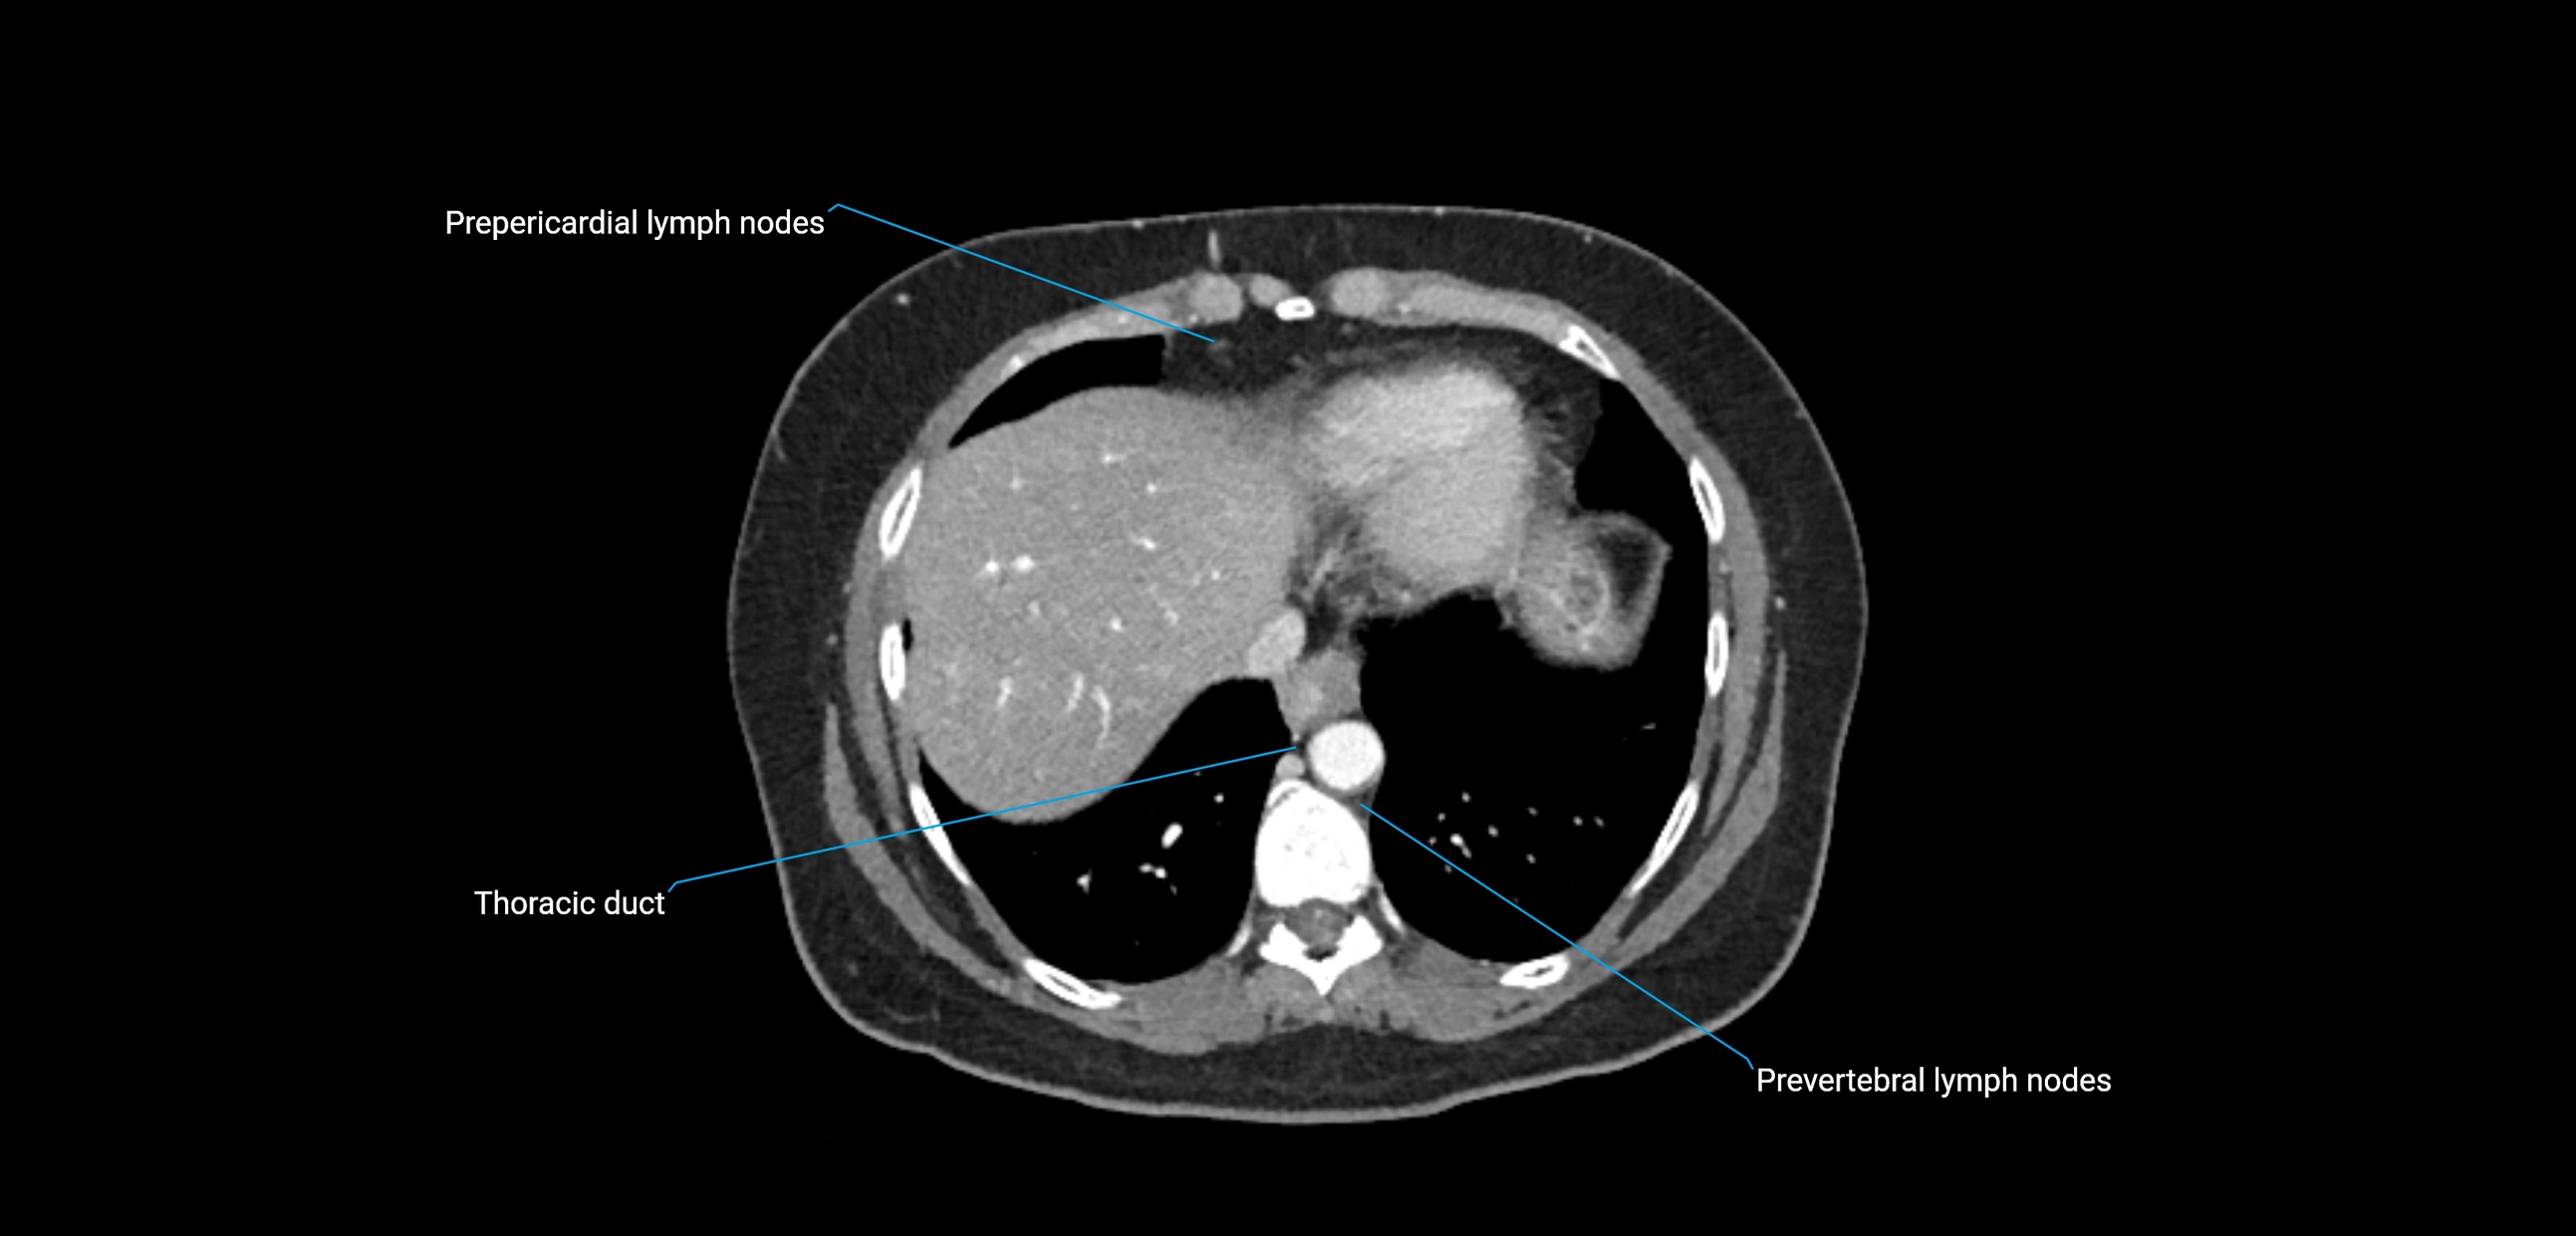

These nodes receive lymph from a wide range of abdominal and pelvic structures. Specifically, they drain lymph from the kidneys, suprarenal glands, gonads (testes/ovaries), uterus, uterine tubes, and pelvic organs, before converging into the lumbar lymphatic trunks, which terminate in the cisterna chyli → thoracic duct.

• Provide a major pathway to the cisterna chyli and thoracic duct

MRI images

image